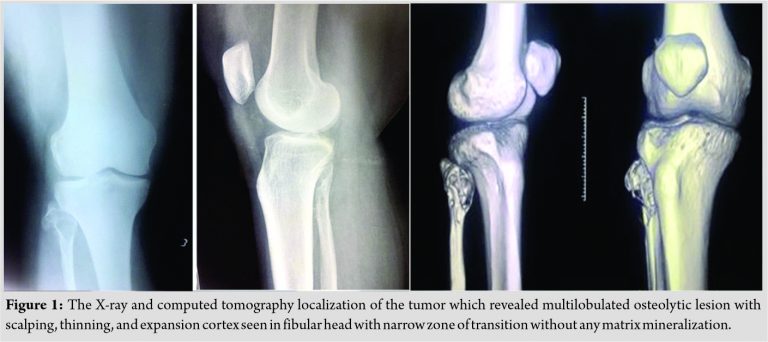

We present a case report of a 38-year-old female who presented with difficulty in walking for the past 5 months associated with pain in the knee for the past 3 months. The pain was dull aching in nature, mild intensity. There was no diurnal variation. Physical examination showed mild tenderness. Overlying skin was normal with restricted range of movement due to pain. Blood investigations were under normal limits. On evaluation radiologically, an expansile osteolytic lesion located in the head of the fibula with thinning and septations measuring 33 × 25 × 18 mm noted. Narrow zone of transition and no matrix mineralization noted. Cortex discontinuity noted in the lateral aspect. Joint space was normal and proximal tibial shaft appeared normal and soft tissue component was noted as shown in (Fig. 1).